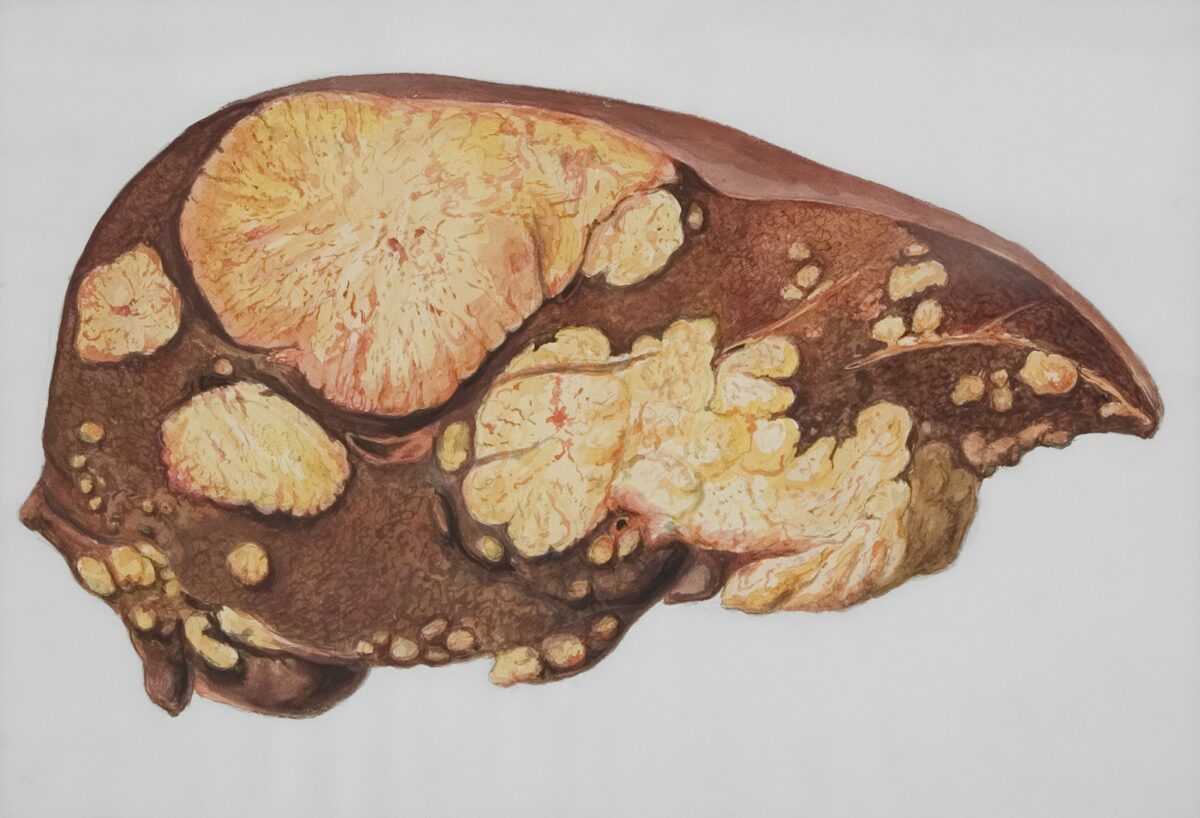

1. Pečeň má výnimočnú schopnosť regenerácie

Pečeň je jediný ľudský orgán, ktorý sa dokáže úplne zregenerovať, a to aj po vážnom poškodení. Vedci zistili, že sa pri tom preprogramuje a aktivuje gény typické pre embryonálny vývoj. Vďaka tomu sa pečeň dokáže obnoviť do pôvodného stavu, akoby sa nič nestalo. Táto schopnosť z nej robí jedinečný orgán v celom ľudskom tele.